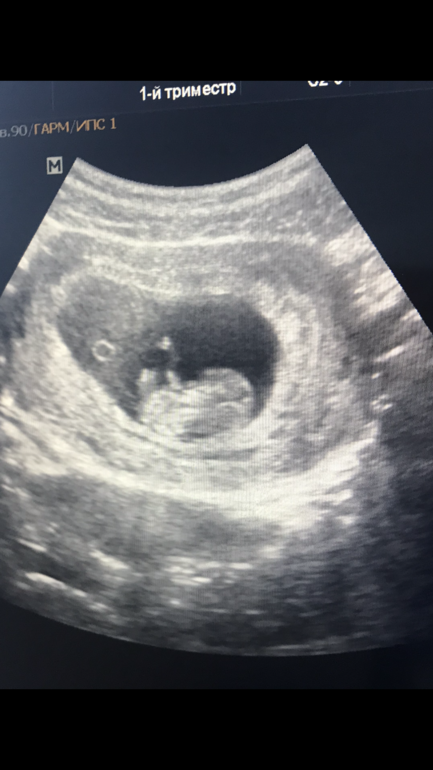

Рядом ножка и бугорок , второй ножки не видно.Вот фото сына

Вот фото 12 недель и 3 дня. 1 скриннинг у генетика. Пол правда тогда никто не сказал и не пытался предположить. Уже потом узнали, что это мальчишка